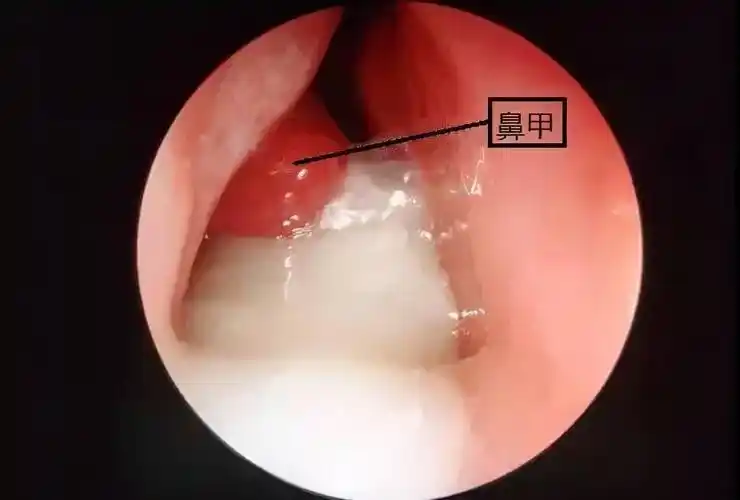

宝宝流这种鼻涕,建议尽快就医_鼻腔